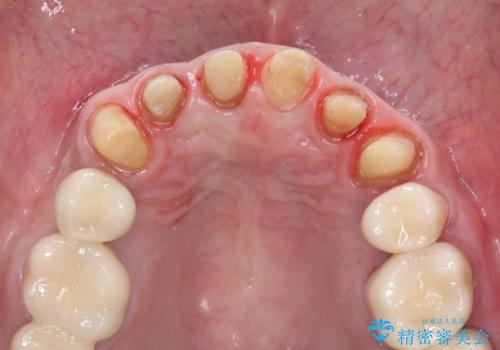

- 「少しずつ色々な箇所が悪くなり、歯医者に通い続けている。全ての歯を長持ちするような状態にできるような治療を受けたい。」、と全顎・総合的な治療を希望され来院されました。

根管治療・矯正治療・歯周外科・セラミック補綴を含む様々な治療オプションを駆使し、長期間良好な状態に保てるような治療計画を立案します。

矯正治療を絡めた総合的な治療をお行なったことで、理想的な咬合関係を確立し安定した噛み合わせで仕上げることができました。

また歯周外科を行うことで歯ぐきの腫れを改善し、清掃性を高めています。